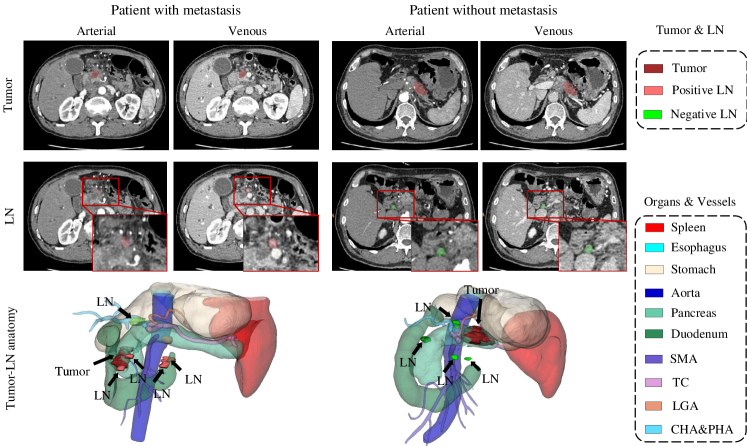

In this paper, we tackle the LN metastasis status prediction problem in patients with PDAC by first segmenting and identifying instances of LNs and then classifying the patients into metastasis-positive or -negative group. LNs are tiny structures that anatomically locate surrounding organs and vessels. Their locations have been mapped into 18 stations that are relevant for pancreatic cancer tumor according to their relative positions against adjacent anatomical structures, as defined by Japan Pancreas Society (JPS)[20] (see Supplementary Table 1 in the supplementary material for details). Examples of their spatial distribution are shown in Fig. 1. Metastasis happens when cancer cells spread from the primary tumor to LNs, causing enlargement of LNs and other underlying changes. Response Evaluation Criteria in Solid Tumors (RECIST) criteria [21] defines the criteria for LN metastasis suspicion, i.e., nodes with short axis greater than 10mm, heterogeneity and central necrosis. However, these criteria are not pathognomonic since there exist false negatives associated with small node micrometastases and false positives with inflammatory nodes larger than 10mm in short axis. Hence, finding LNs in CT images is quite time-consuming and can be inconsistent depending on radiologists’ subjective experiences. It is ambiguous for radiologists to identify nodal positivity accurately from CT without referring to pathology reports. The gold standard for determination of metastasis is based on post-operative pathological evaluation of pancreatectomy specimens. Automated yet reliable pre-operative LN segmentation and identification are highly desirable for patient surgical or RT treatment planing.

Attention Map Generation. To explicitly capture and model the lymphatic anatomy, attention computation is implemented as a pre-defined geometric mapping function from organvessel distance maps. An example of attention map generation process is shown in Fig. 3. Specifically, given a multi-phase input CT volume , we first obtain organvessel segmentation mask using nnUNet [27] model trained with 19 classes of annotations. Ten classes among them involved with 17 LN stations are used (see Supplementary Table 1 in the supplementary material for the definition of LN stations), i.e., spleen, esophagus, stomach, aorta, pancreas, duodenum, superior mesenteric artery (SMA), truncus coeliacus and splenic artery (TCSA), left gastric artery (LGA), common hepatic artery and proper hepatic artery (CHAPHA). Note that station 15# (LNs along middle colic artery) is left aside here since it is related to distant metastasis that rarely happens in our patient population. A SDT is applied to each class of the segmentation mask , generating a total of 10 organ/vessel distance maps where is the index of organ/vessel class. has positive values at the voxels outside the -th organ/vessel and negative scores inside it. Intuitively, LNs are likely to appear within a certain range of distance to each organ/vessel, which requires paying attention to. To obtain the distance-guided attention maps, is passed to an isosceles trapezium-shaped non-linear mapping function (see Fig. 3), formulated as